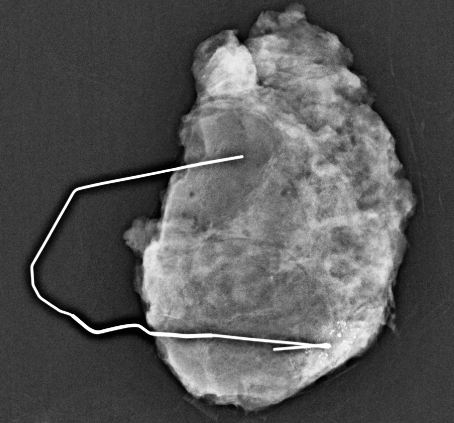

标本验证: 手术切除包含导丝尖端(即目标钙化区域)的组织块后,需立即进行标本钼靶摄片。这是关键质量控制步骤

三、 术后石蜡切片明确诊断

完整切除钙化灶后,最终就交给病理科定“真伪”

术后某患者病检